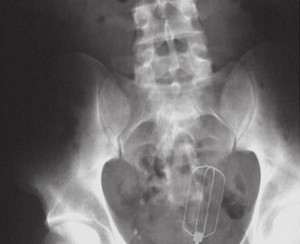

ბილიარდის ბურთი

10 (1)